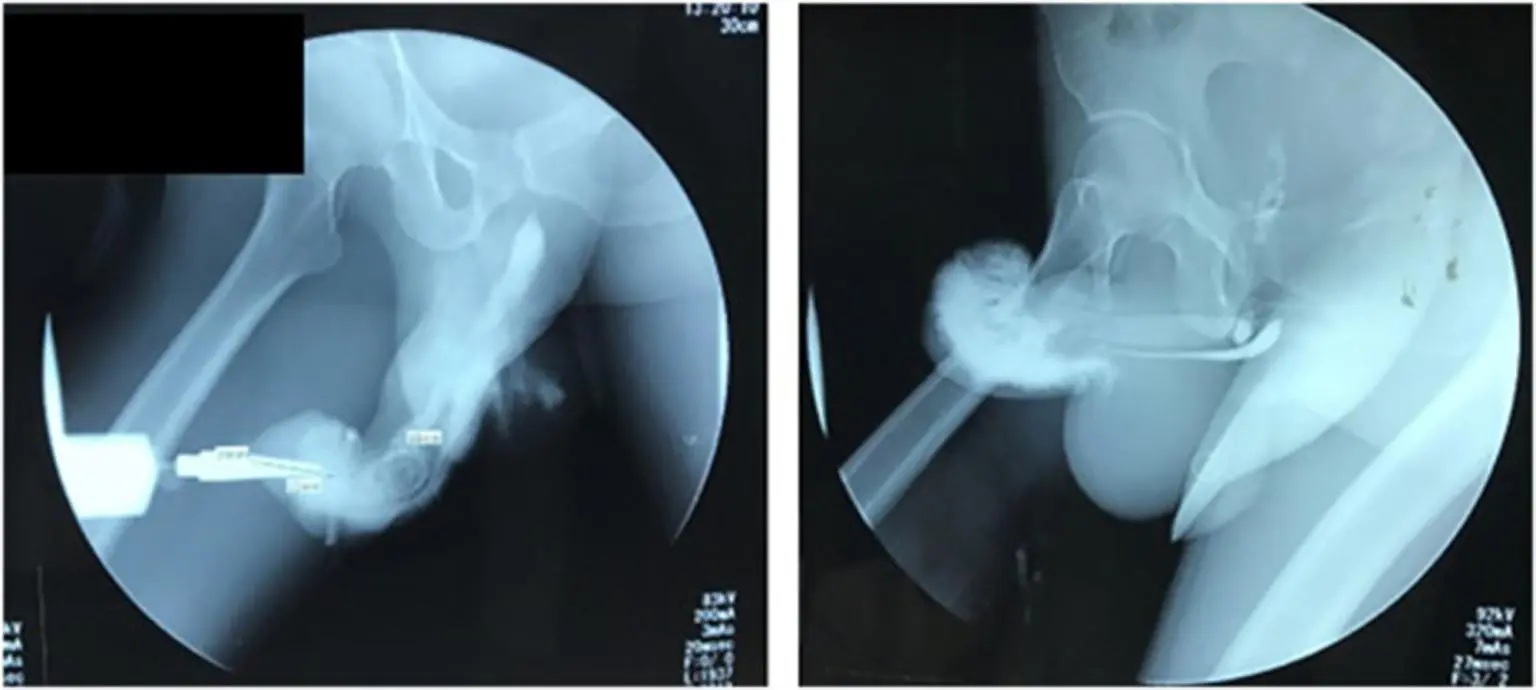

Přesto, že penis neobsahuje žádnou kost, corpus cavernosa se zlomit může. Corpus cavernosa jsou trubičky, které se při erekci naplní krví. Pokud se tyto trubičky při nešetrné manipulaci s penisem ohnou, můžou se porušit, roztrhnout a naplnit mužský penis krví. Tato nehoda potom vede k deformaci penisu, otoku a ztrátě sexuálních funkcí.